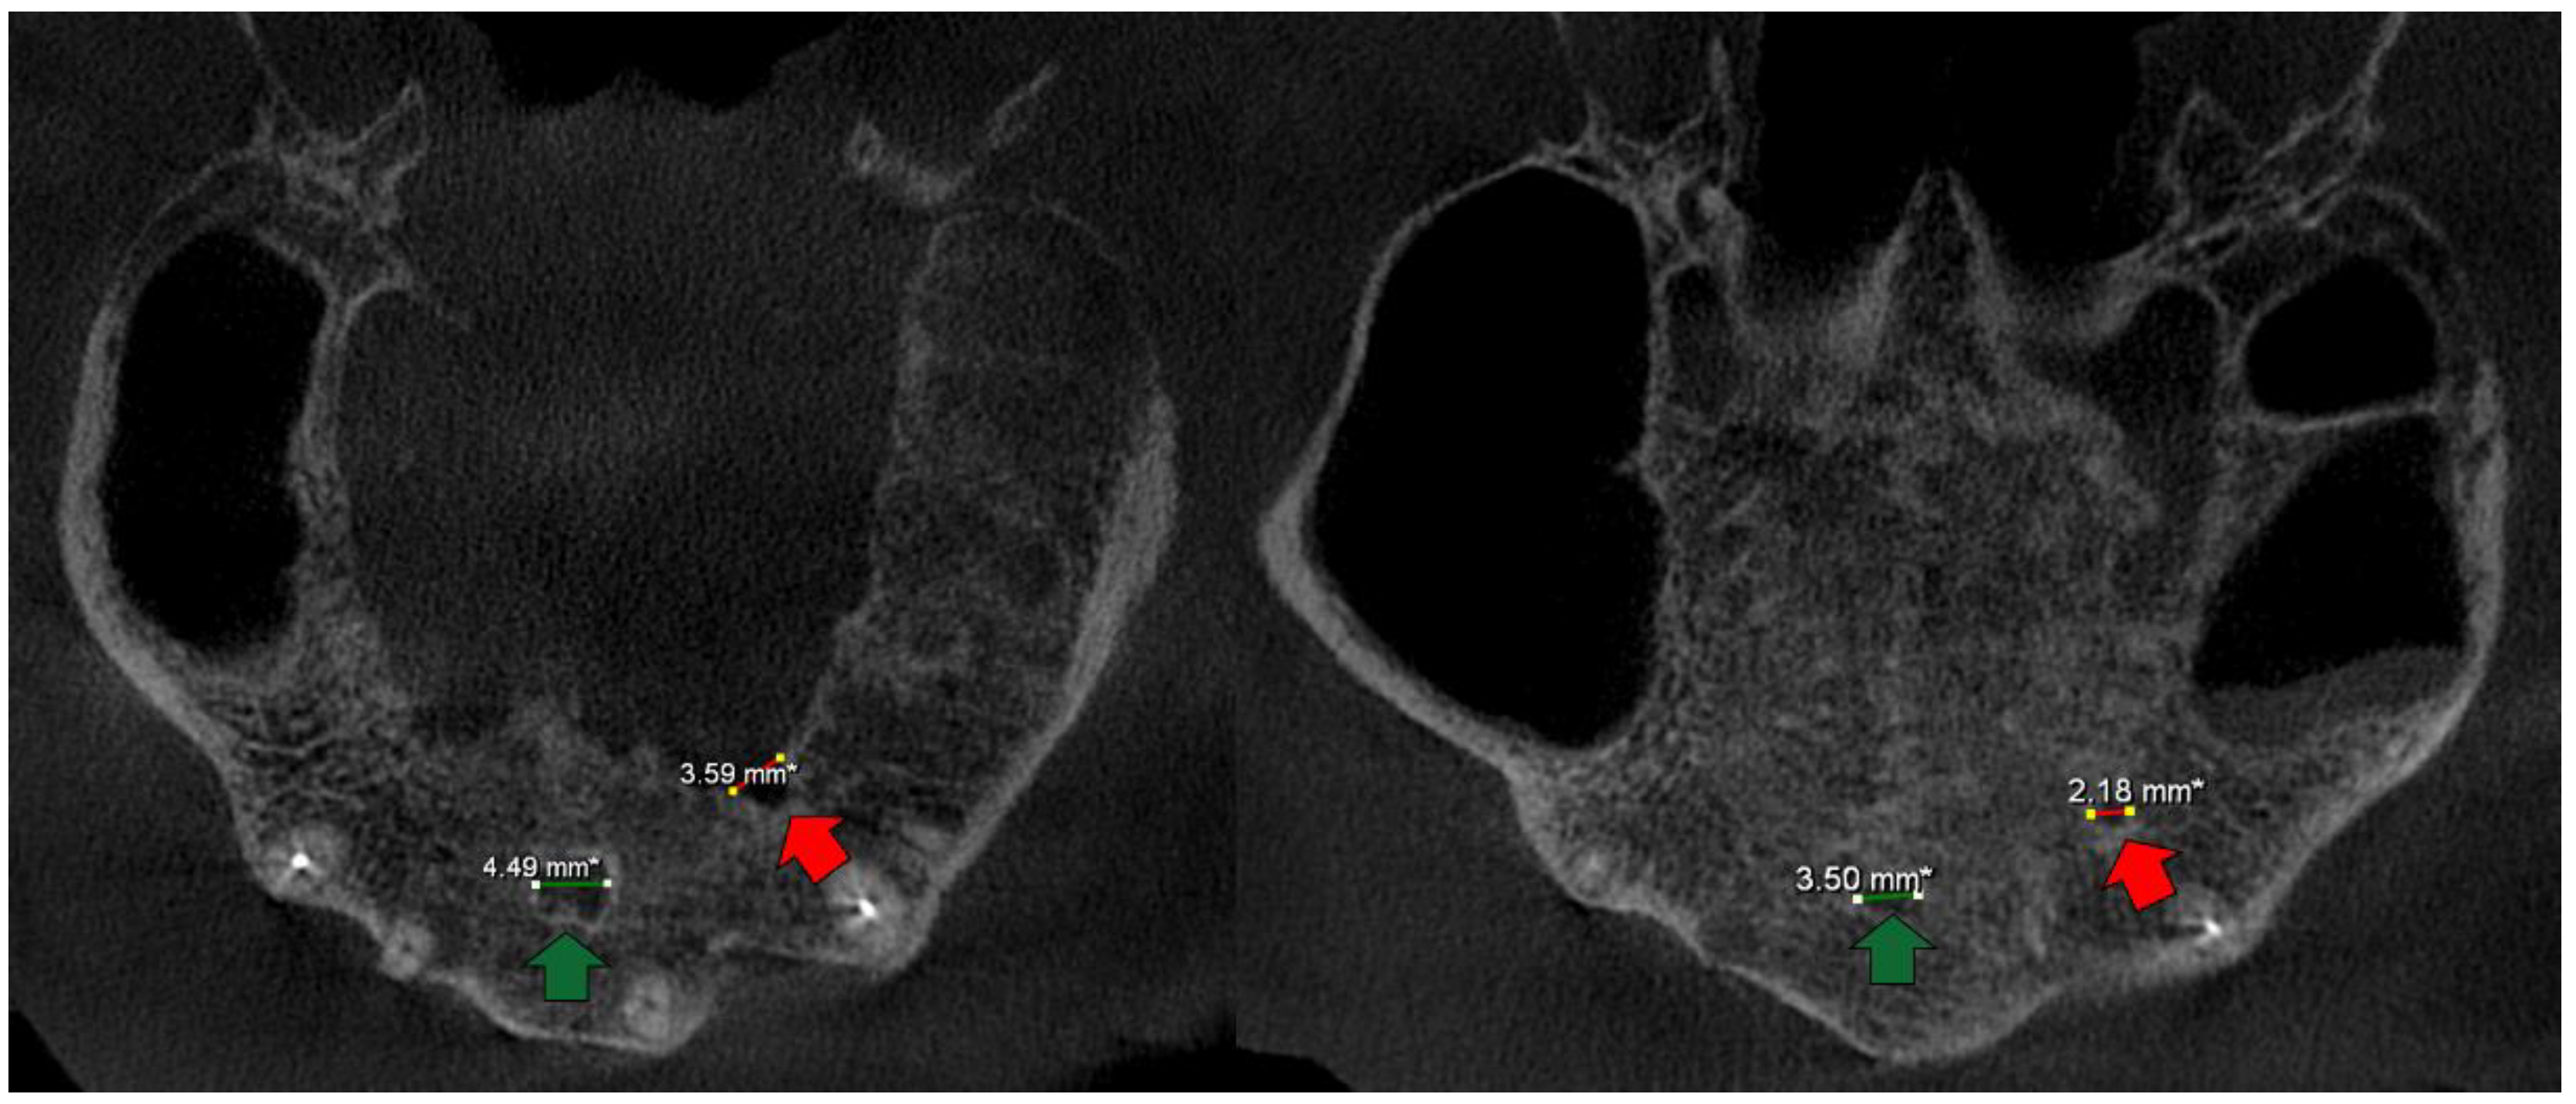

- A case with an AC which was in contact with a radicular cyst (Figure 1);